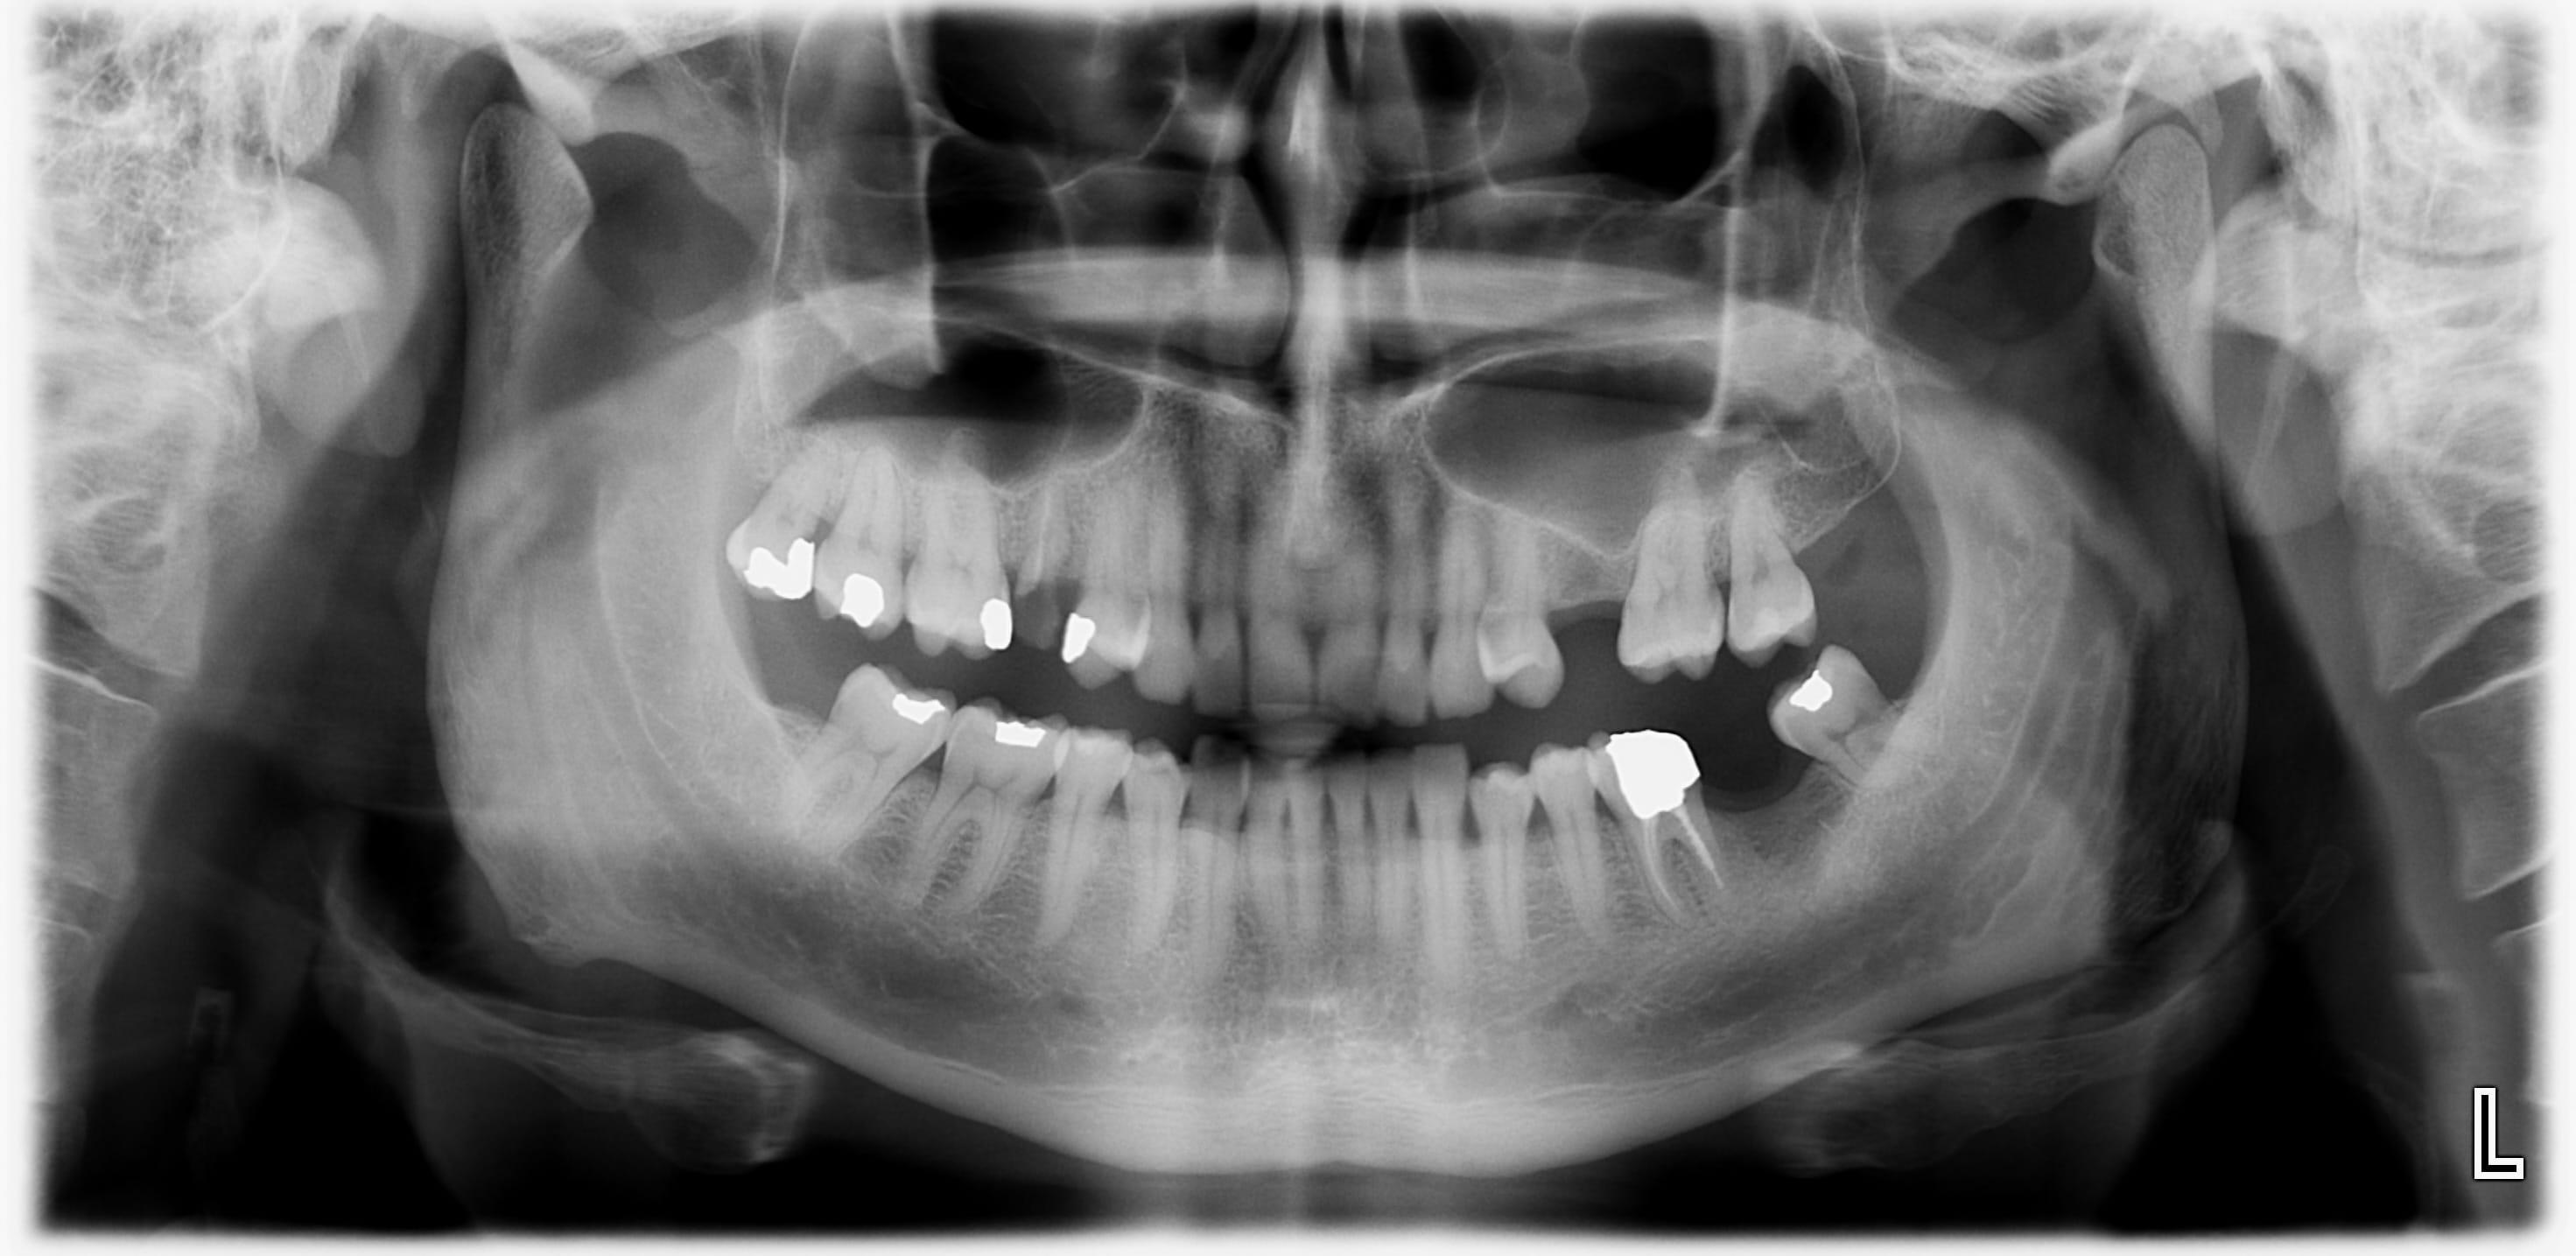

Image OPT nerf mandibulaire double ?

j'ai reçu un patient avec un antécédent de fissure de la mandibule suite à un choc il y a 25 ans (branche dans un bois)

Je trouve l'image du nerf dentaire dans la branche montante bizarre. C'est comme si le nerf mandibulaire se dédoublait.

Avez-vous déjà vu ce genre d'image radiologique?